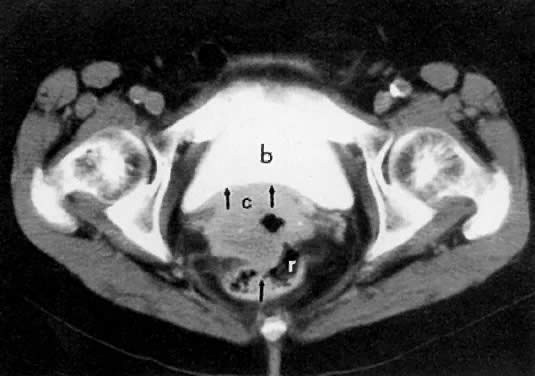

Fig. 2. Axial T1-weighted MR ( A) and CT ( B) images of the pelvis in a patient with cervical cancer show right parametrial extension of tumor ( arrow ). Note the normal left parametrium ( arrowhead ). Proven stage IIB. ( s, sigmoid; b, bladder; r, rectum.)

CT can be helpful in the diagnosis of parametrial invasion and can be used in conjunction with the physical examination in differentiating stage I cervical carcinoma from stage IIB or more advanced disease. The criteria used to diagnose parametrial invasion include irregularity or poor definition of the lateral cervical margins, prominent parametrial soft-tissue strands, eccentric soft-tissue mass (see Fig. 2B), and obliteration of the periureteral soft-tissue planes without hydroureter (Fig. 11). Prominent strands can be seen with inflammation, but are more commonly seen with tumor invasion. One should be careful in diagnosing parametrial invasion in patients with asymmetry of the cervix because tampon insertion occasionally causes angulation of the uterus. The reported accuracy of parametrial involvement by CT is 70%, positive predictive value 33%, and negative predictive value 67%.9